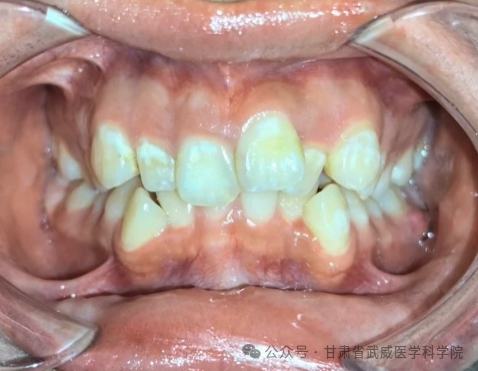

牙列不齐,医学上称为“错颌畸形”,是指儿童在生长发育过程中,由先天的遗传因素或后天的环境因素(如疾病、口腔不良习惯、替牙异常等)导致的牙齿、颌骨、颅面的畸形。

·清洁死角多: 牙齿重叠交错,容易藏匿食物残渣和牙菌斑,刷牙刷不干净。

·引发牙病: 极易导致龋齿(蛀牙)、牙龈炎、牙周病(牙龈红肿、出血、萎缩)。

·异常磨损: 牙齿排列不齐会导致咬合力量分布不均,个别牙齿过度磨损,出现酸痛、敏感甚至断裂。